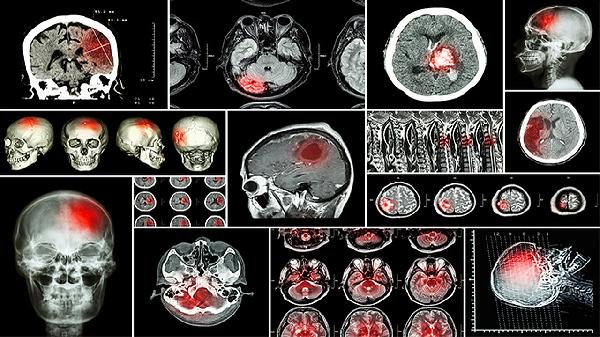

4、脑血管疾病

脑血管疾病可能与高血压、高血脂等因素有关,通常表现为头痛、呕吐、肢体无力等症状。脑血管疾病如脑梗死可能导致半个后脑勺木连着脸麻。可在医生指导下使用阿托伐他汀钙片、氯吡格雷片、胞磷胆碱钠胶囊等药物进行治疗。严重时需考虑手术治疗。日常需控制基础疾病,定期复查。